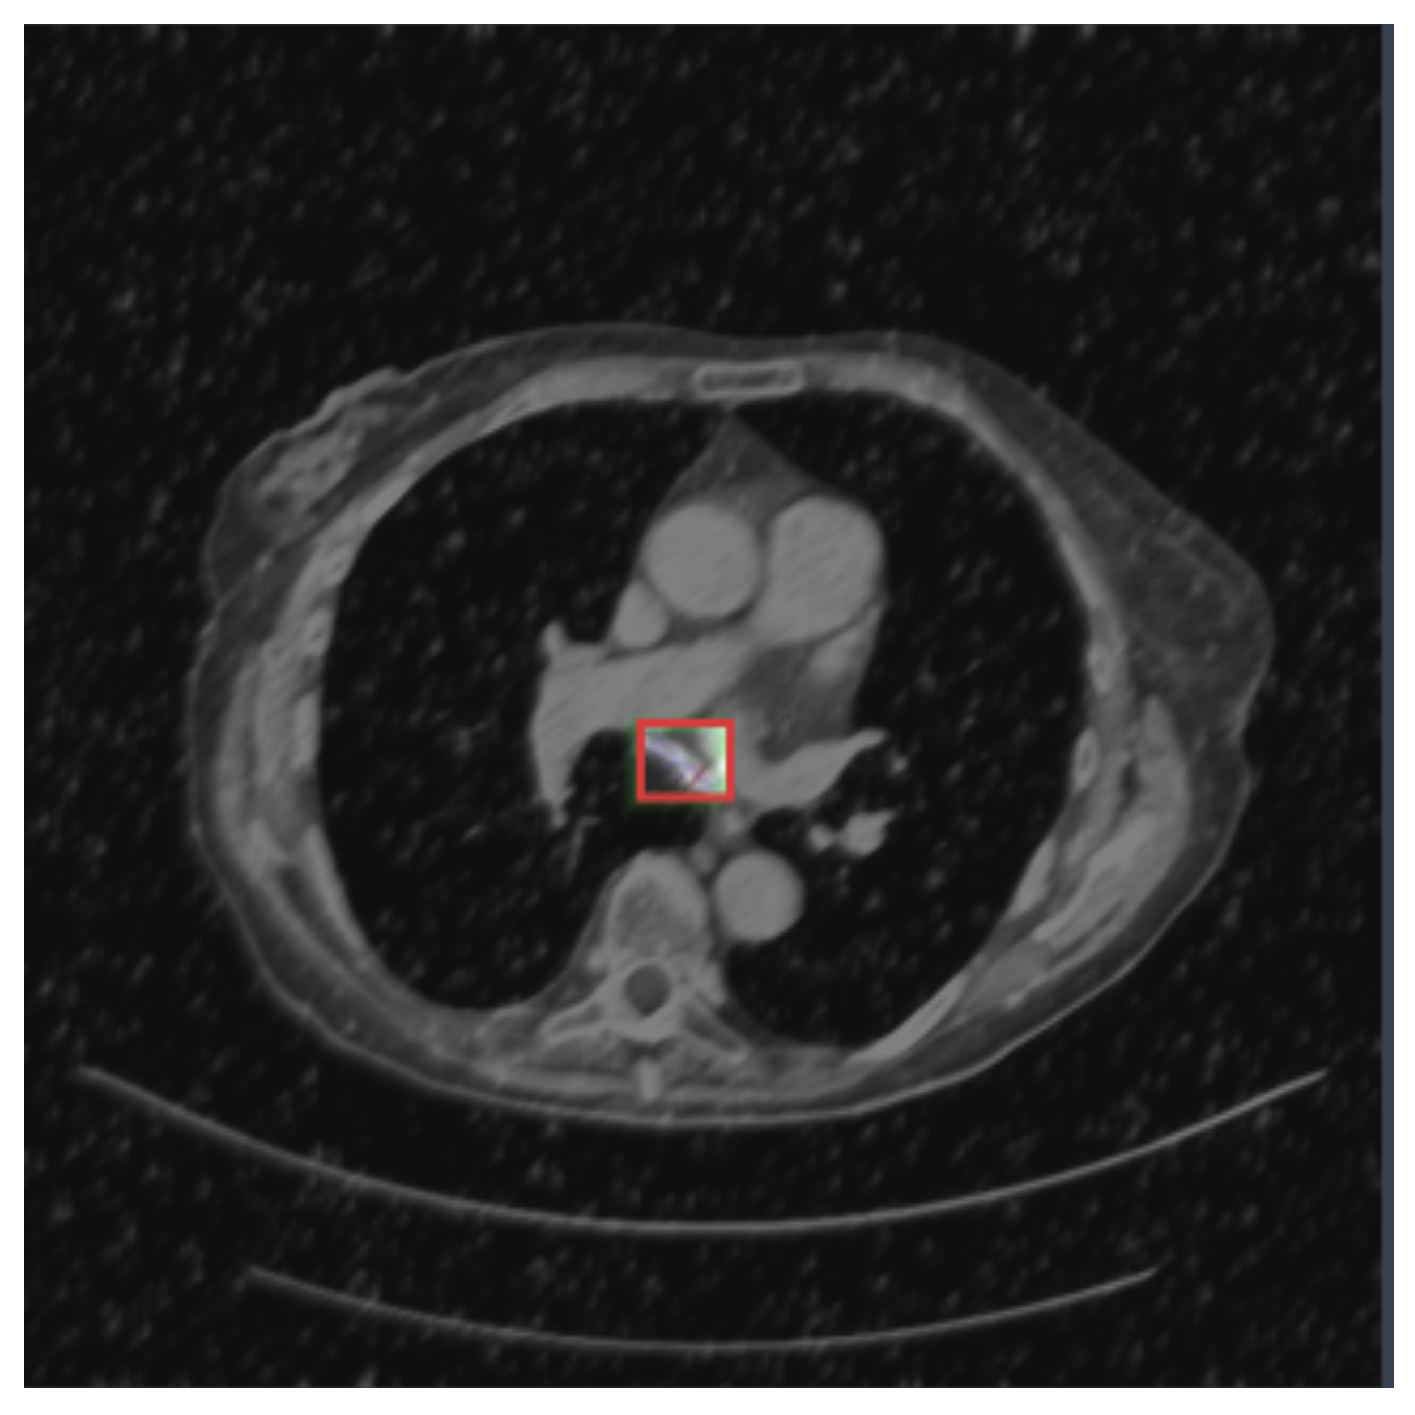

| Class | Image | Instances | Box (P) | Box (R) | Box (mAP50) | Box (mAP50-95) |

|---|---|---|---|---|---|---|

| all | 324 | 332 | 0.757 | 0.738 | 0.71 | 0.488 |

| adenocarsinoma | 324 | 45 | 0.815 | 0.685 | 0.713 | 0.492 |

| cancer | 324 | 46 | 0.572 | 0.783 | 0.588 | 0.467 |

| nodule | 324 | 241 | 0.884 | 0.747 | 0.831 | 0.505 |

| Class | Image | Instances | M (P) | M (R) | M (mAP50) | M (mAP50-95) |

| all | 324 | 332 | 0.75 | 0.733 | 0.708 | 0.438 |

| adenocarsinoma | 324 | 45 | 0.815 | 0.685 | 0.734 | 0.539 |

| cancer | 324 | 46 | 0.572 | 0.783 | 0.588 | 0.366 |

| nodule | 324 | 241 | 0.865 | 0.73 | 0.802 | 0.41 |